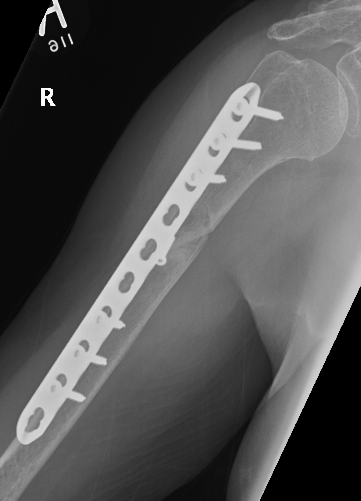

Humeral Fracture SegmentalHumeral Plate LateralHumeral Plate Long AP

Segmental fracture ORIF